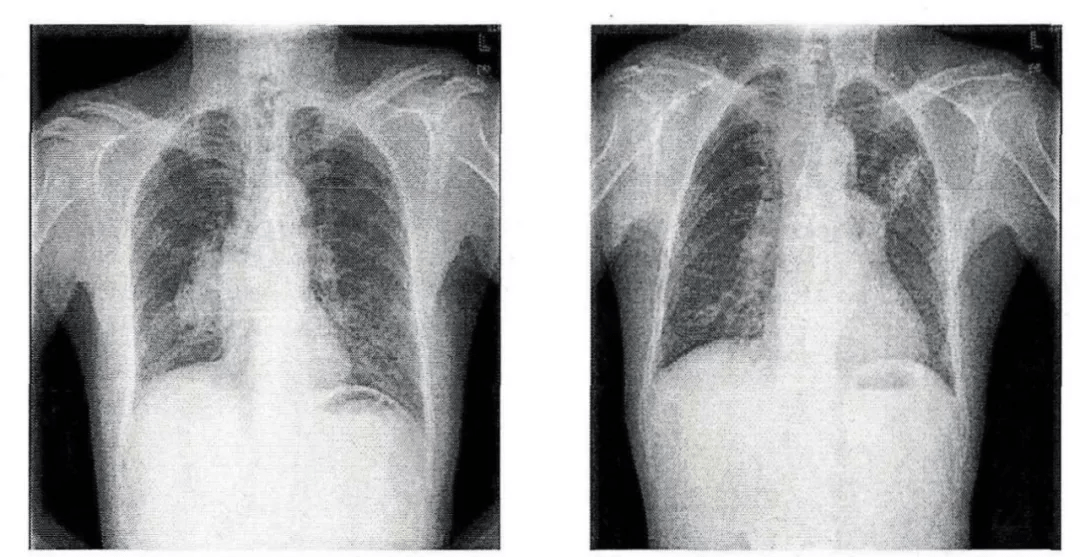

这样的充盈缺损是肺栓塞